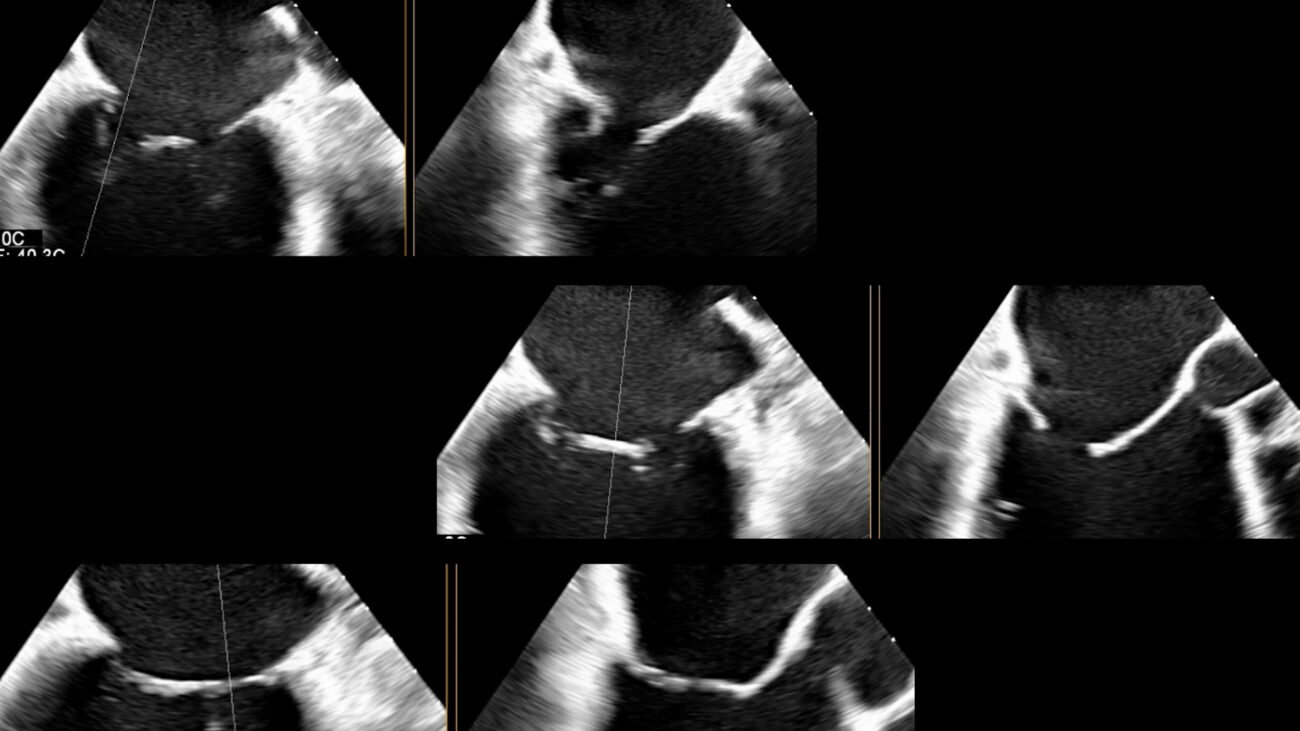

L’ecografia 3D per lo studio delle valvole cardiache. Applicazioni sulla valvola mitrale

Questa videolezione si focalizza in particolar modo sulle applicazioni sulla valvola mitrale. Qui trovi la lezione precedente sui Principi base.